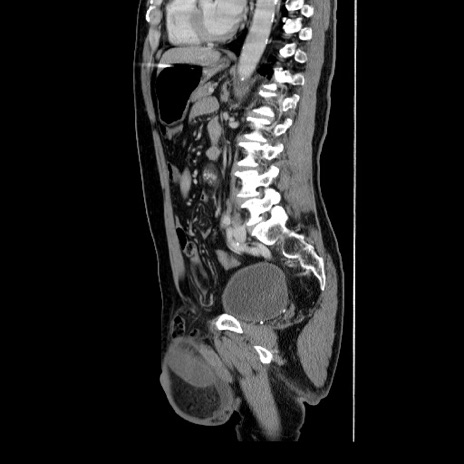

症例34(矢状断像)

【症例】60歳代 男性

【主訴】右鼠径部膨隆

【現病歴】1年程前より右鼠径部膨隆あり。自己にて還納可能だったため放置していた。3時間前より右鼠径部の脱出を認め、還納困難となり受診。

【既往歴】高血圧

【身体所見】右鼠径部に小児頭大の膨隆あり。弾性硬であり、用手還納は困難。左鼠径部にも膨隆を認める。脱出はなし。

【データ】WBC 15500、CRP 測定なし